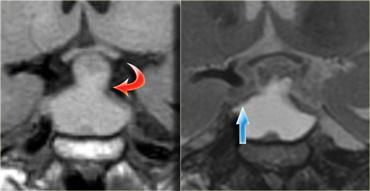

Bên trái là một ví dụ khác về u tuyến yên đại tuyến.

Tổn thương bắt đầu từ hố yên, vốn đã bị giãn rộng, và lan rộng vào bể dịch não tủy trên yên (suprasellar cistern).

Lưu ý hình ảnh ‘người tuyết’ kinh điển được tạo ra do sự thắt nghẽn bởi màng hoành yên.

Chú ý mức dịch-máu (blood-fluid level), cho thấy có xuất huyết.

Tầm quan trọng của việc quan sát hướng nghiêng của các lá màng hoành yên đã được đề cập trước đó.

Trên các hình ảnh chuỗi xung T2W bên phải, có thể thấy các lá màng hoành bị đẩy lên trên bởi khối u đại tuyến này, vốn bắt đầu từ hố yên và đang phát triển lên trên.

Một tổn thương có nguồn gốc từ phía trên hố yên và phát triển xuống dưới sẽ đẩy các lá màng hoành theo hướng ngược lại (điều này có thể thấy trong trường hợp u màng não chẳng hạn).